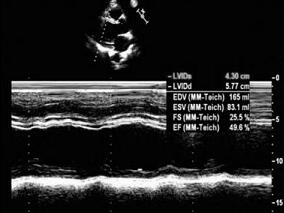

1小时条评论中年男性,动脉导管未闭术后阵发性心悸,最终超声心动图查明缘由。本例心室心尖部室壁瘤有何特殊性?缘何归因医源性?又有哪些心脏手术可能引起医源性在心室心尖部室壁瘤?这些问题待您解答。 病例摘要 主诉 男性,42岁。主因动脉导管未闭缝扎术后14年,阵发性心悸6...